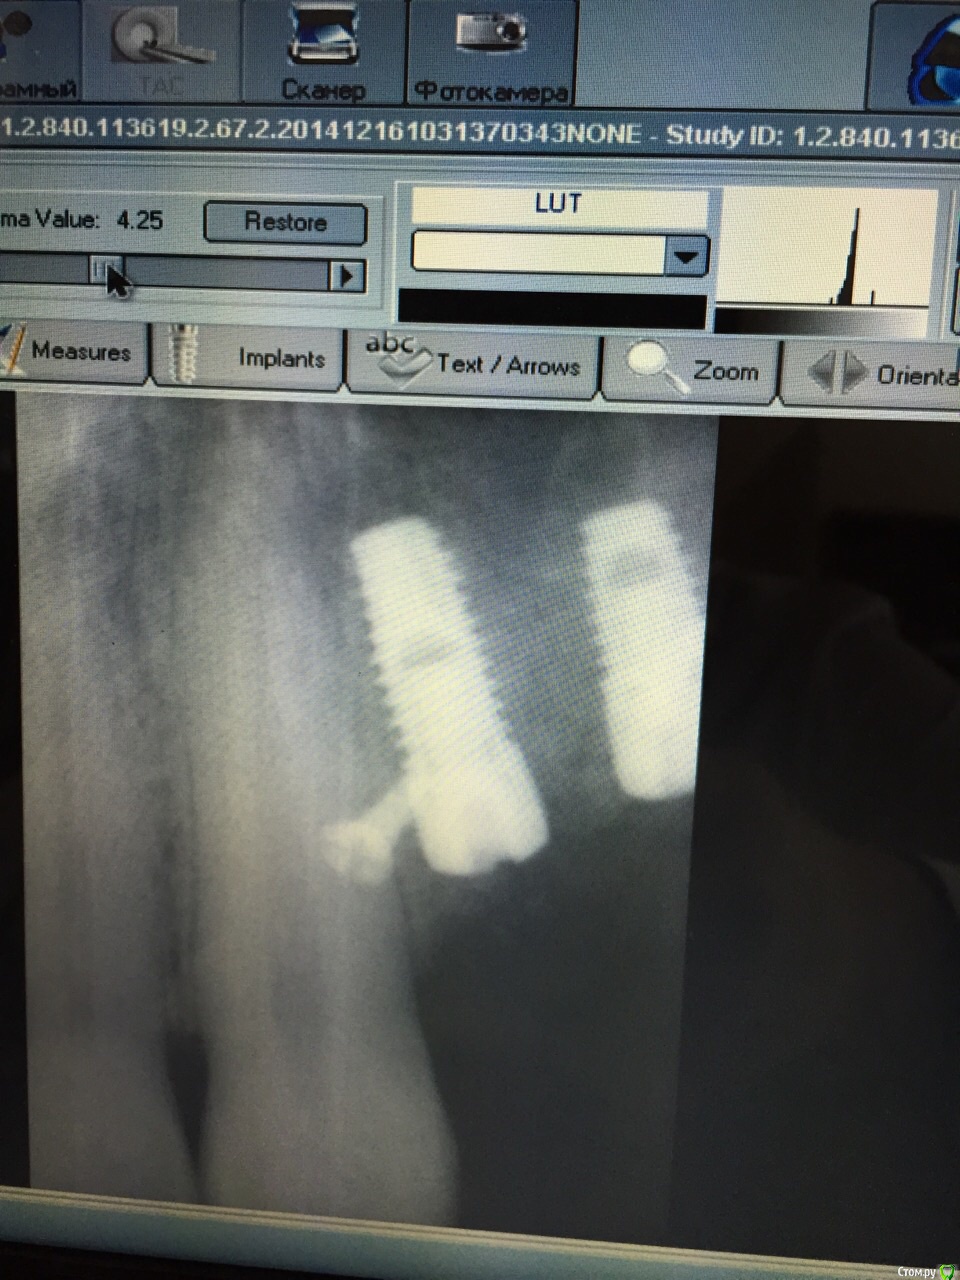

Заурбек Опубликовано 17 декабря, 2014 Автор Поделиться Опубликовано 17 декабря, 2014 спасибо большое за скорый ответ))))вот снимок Ссылка на комментарий

kriokov Опубликовано 17 декабря, 2014 Поделиться Опубликовано 17 декабря, 2014 вот снимок на снимке ничего , чтобы насторожилоТрудно что то советовать не глядя. Может отпунктировать в обл выбухания, если прогрессировать будет? Подождем мнение коллег,Ожог если , то боли с 3 суток, обычно. В Вашем случае- с шестых, и припухлость по переходной , не совсем в клинику ожога укладывается. Ссылка на комментарий